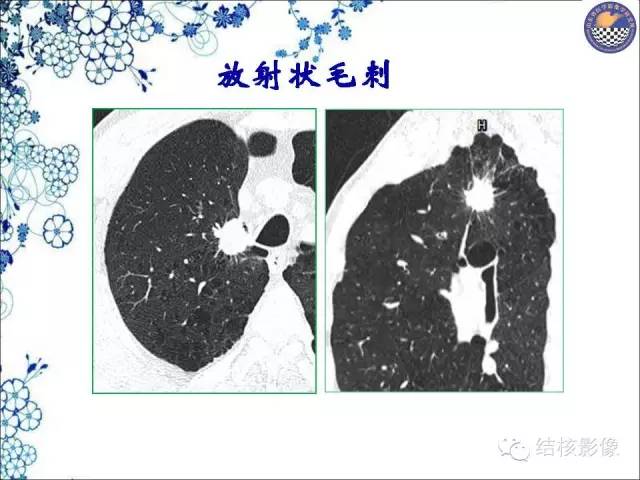

【PPT】肺癌CT高危征象解析